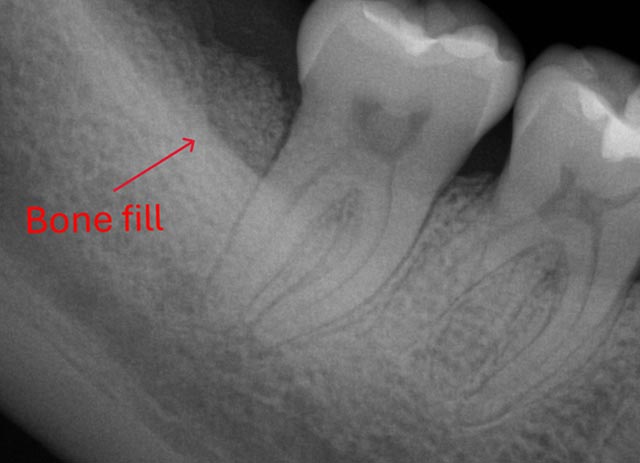

Tooth Bone Grafting - Before And After

Tooth bone grafting – before procedure

Tooth bone grafting – after procedure